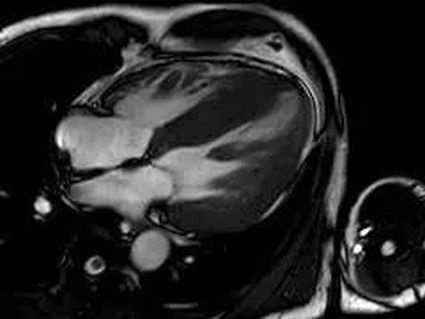

2.心脏的功能问题。比如:左心室、右心室的射血能力(EF值)等。

3.心肌的活动情况。比如:心肌的收缩、舒张能力的减低,局部心肌的异常活动等。

1.借助心脏电影,完成心功能分析。

总之,心脏磁共振检查具有无电离辐射、优良的软组织对比分辨率、大视野、任意平面成像的特点,能够“一站式”获得心脏形态、功能及冠状动脉的所有信息。是评估坏死心肌,心肌纤维化及瘢痕成分的有效影像学检查方法,也是评价心脏结构和功能的金标准。